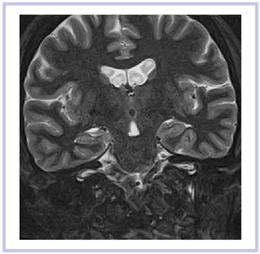

real IRは,薄いスライス厚でもコントラスト分解能に優れた撮像法である。痴呆性疾患などで注目されている海馬領域を中心に,T1強調の2Dスキャンを行った(図11)。画像を拡大すると,内部のコントラストも非常に良好なことがわかる(図12)。同様にT2強調の2D-STIRでも,比較的良好な画像が得られている(図13)。海馬内部の微細構造も,高い空間分解能で描出することが可能となっている。

![]() 図11 海馬領域のreal IR |

![]() 図12 図11の拡大画像 |

![]() 図13 海馬領域のT2強調2D-STIR |